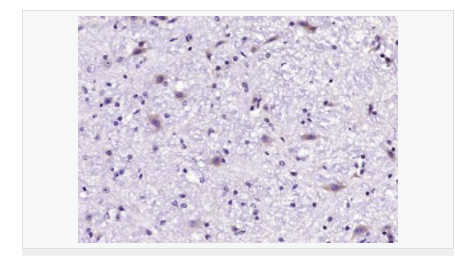

| 產品應用 | WB=1:500-2000 IHC-P=1:100-500 IHC-F=1:100-500 ICC=1:100-500 IF=1:100-500 (石蠟切片需做抗原修復) not yet tested in other applications. optimal dilutions/concentrations should be determined by the end user. |

| 產品介紹 | GLRB (Glycine receptor beta) is a neurotransmitter-gated ion channel concentrated within the spinal cord and brainstem. Expression is also observed in several upper brain regions including the cortex, cerebellum, hippocampus and amygdala. Binding of glycine to GLRB increases the chloride conductance and thus produces hyperpolarization (inhibition of neuronal firing), controlling spinal reflexes and locomotor behavior. Function: The glycine receptor is a neurotransmitter-gated ion channel. Binding of glycine to its receptor increases the chloride conductance and thus produces hyperpolarization (inhibition of neuronal firing). Subunit: Pentamer composed of alpha and beta subunits. Interacts with GPHN Subcellular Location: Plasma membrane; multi-pass membrane protein. DISEASE: Defects in GLRB are the cause of hyperekplexia type 2 (HKPX2) [MIM:614619]. HKPX2 is a neurologic disorder characterized by muscular rigidity of central nervous system origin, particularly in the neonatal period, and by an exaggerated startle response to unexpected acoustic or tactile2 stimuli. Similarity: Belongs to the ligand-gated ion channel (TC 1.A.9) family. Glycine receptor (TC 1.A.9.3) subfamily. GLRB sub-subfamily. SWISS: P48167 Gene ID: 2743 Database links: Entrez Gene: 2743 Human Entrez Gene: 14658 Mouse Omim: 138492 Human SwissProt: P48167 Human SwissProt: P48168 Mouse Unigene: 32973 Human Unigene: 275639 Mouse Important Note: This product as supplied is intended for research use only, not for use in human, therapeutic or diagnostic applications. |